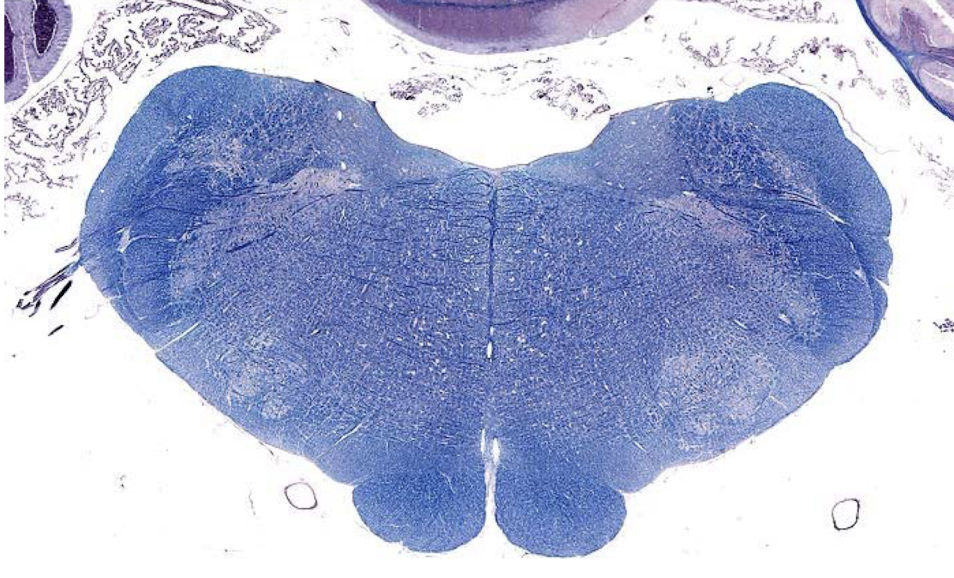

what section of the brain is shown?

middle medulla

- open 4th ventricle

- no trapezoid body

- no olivary nuclei

- pyramids (indicates medulla)